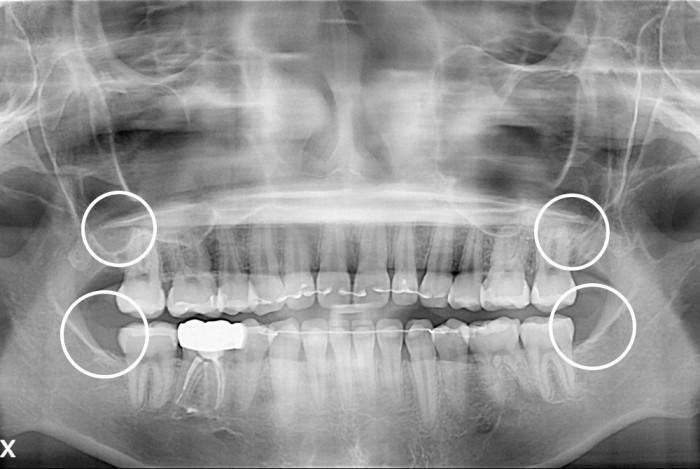

[사랑니] 사랑니

PX20210605_092814_0307_00000000.jpg

치료후 : 2021-06-05

세종치과는 구강악안면외과학 박사이신 원장님이 발치하는 치과입니다.